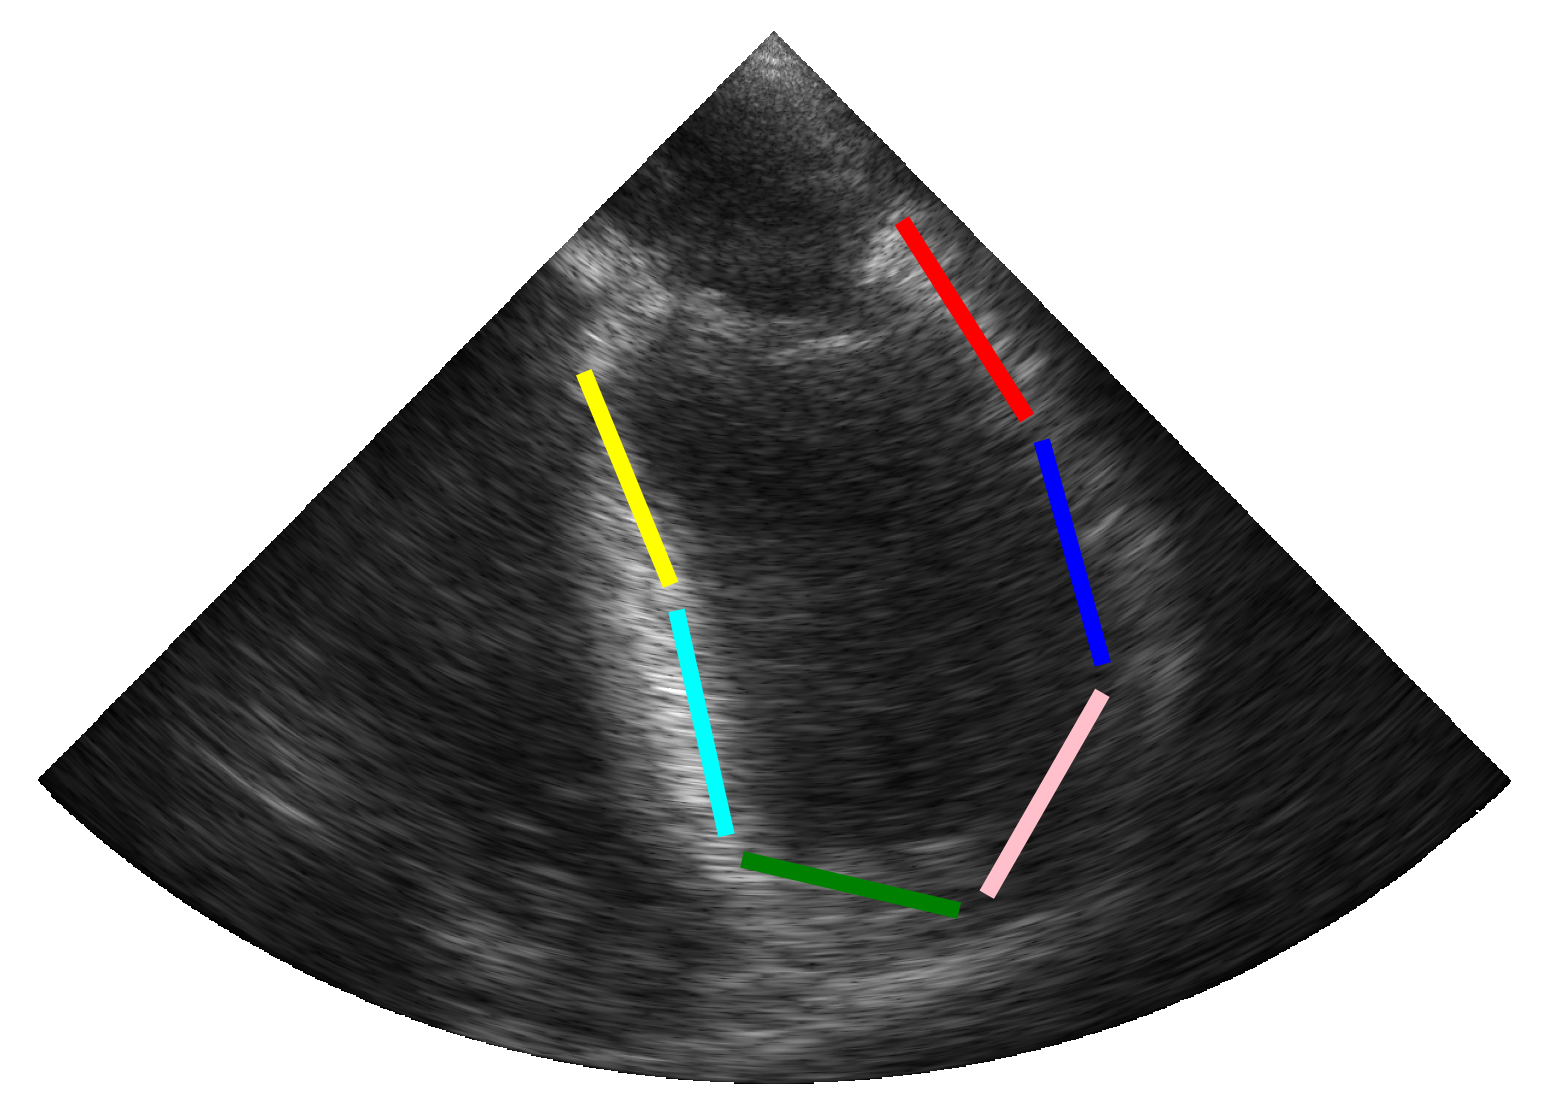

2.3.2 Simulation of Synthetic Infarction

To account for patients with hypokinetic pathologies, we enhanced the simulation pipeline by designing additional scenarios that simulate myocardial infarction in one of the six cardiac segments. Based on the pipeline described above (c.f. Figure 1), a synthetic myocardial motion was first estimated from a real sequence using the same technique as previously described [14]. The longitudinal contraction of myocardial scatterers was then reduced locally (i.e. at the center of a specific segment) following a Gaussian distribution throughout the cardiac cycle. The scatterers in the surrounding tissues were finally designed to compensate for the reduced contractility in order to maintain overall contraction, thus enabling the rest of the pipeline to be preserved.

3.1.3 Local Deformation Abnormalities

We extended our pipeline to simulate myocardial infarction, aiming to assess our model’s ability to detect and adapt to localized hypokinetic dysfunction in cardiac muscle. This was done through an ablation study whose results were given in Table 4. Using the combined strategy, we trained our TeeTracker on the fourth dataset described in Table 1, with and without a fifth dataset involving synthetic infarction. The model trained on the dataset incorporating synthetic infarction demonstrated remarkable generalization to regional variations in myocardial contraction, with a mean distance error of 0.37 0.06 mm across all segments and 0.36 0.11 mm on infarcted segments. Moreover, this model outperformed the one trained without synthetic infarction, which achieved a mean distance error of 0.58 0.14 mm across all segments. These results also hold for the clinical metrics, where TeeTracker trained on the combined dataset with synthetic infarcts achieved the best scores with a mean difference (95% limits of agreement) of 0.14% (-2.60% to 2.88%) for SLS and a mean difference (95% limits of agreement) of 0.11% (-0.69% to 0.91%) for GLS. The quality of these results was further validated through the Bland-Altman plots provided in Figure 4. Finally, Figure 5 shows the reference and segmental strain curves estimated by our TeeTracker models from a simulated sequence with an infarct region. Visual inspection of the curves reveals that our best model successfully identified and localized the infarcted segments, maintaining a coherent global contraction pattern while accurately reflecting regional dysfunction. These results demonstrate the ability of TeeTracker to detect and quantify myocardial abnormalities, thereby enhancing its clinical applicability for real-world TEE data.